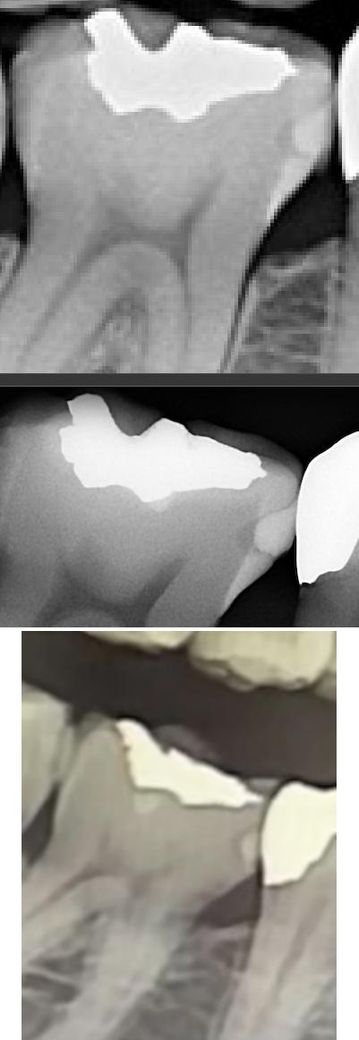

안녕하세요, 사진에 보이는 인접면 충치를 치료해야 하나 고민이 있습니다. 위부터 순서대로 재작년 11월, 작년 8월, 올해 1월에 찍은 사진입니다. 오른쪽에 금 인레이를 해주셨던 선생님은 3년 정도 더 관리하면서 지켜보자고 하셨고 어떤 치과에선 치료하는게 좋을거 같다고 했습니다. 나름 열심히 관리하면서 지켜보고 있는데, 이게 관리하면서 지켜볼만한 충치인지 아니면 치료를 해야할지 고민입니다.

충치라기보다는 형태를 봤을 때 처음 때울때 파낸만큼 채우지 못해서 안쪽에 공간이 생긴 것으로 보입니다. 충치가 생기기 전까지는 크게 문제가되지는 않겠지만 한번 시작되면 급속도로 썩을수는 있어서 걱정되신다면 때워주는 것이 맞고 정기적으로 검사해볼 수 있다면 지켜보셔도 괜찮겠습니다.

수복물 하방 이차충치의 경우 그냥 안쪽에서 자연 발생하거나 그러진 않습니다 수복물에 결함, 틈이 있어서 그 틈으로 음식물과 침이 들어가 충치를 유발하는 것이고요. 그대로 두면 계속 충치가 커져 신경을 침범할 수도 있습니다. 너무 늦지 않게 처치하는 것을 권장드립니다.

사진으로 보았을 경우에는 치료를 한 내부에 다시 충치가 생긴 것으로 보입니다. 이런 경우 해당 부위에 충치를 치료하기 위해서는 충전한 재료를 제거하고 다시 레진으로 충전을 해줄 수 있습니다.